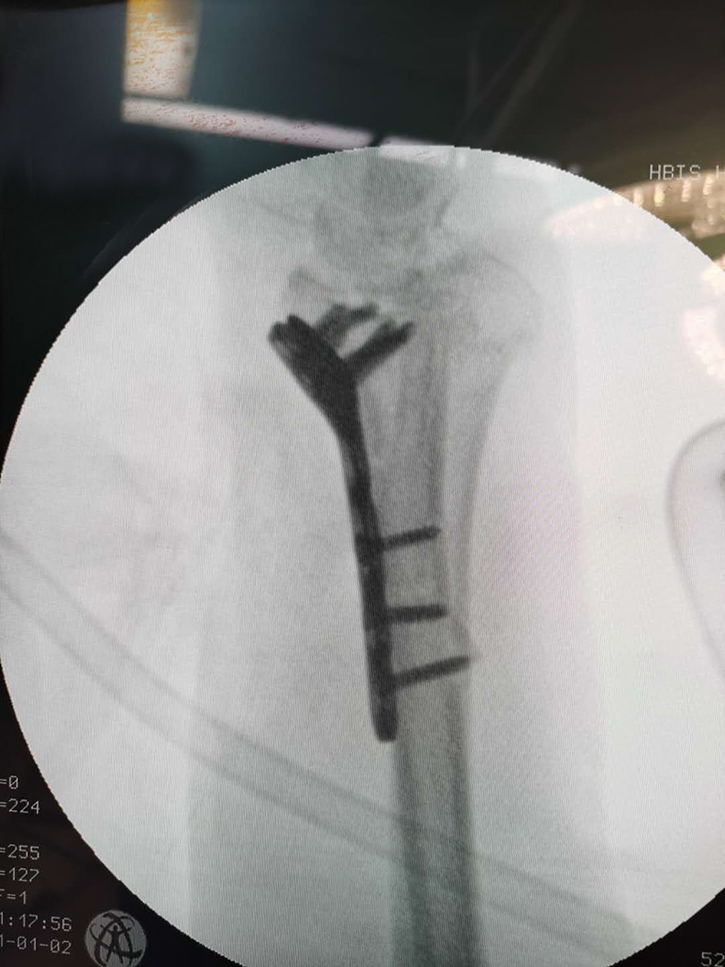

常州鼎健醫(yī)療器械有限公司、弘慈醫(yī)療集團(tuán)均屬于中信產(chǎn)業(yè)基金控股的醫(yī)療企業(yè),而鼎健醫(yī)療作為弘慈醫(yī)療重要戰(zhàn)略合作伙伴的骨科耗材供應(yīng)商,從弘慈醫(yī)療旗下弘慈醫(yī)院的臨床需求出發(fā),提供最適宜的骨科耗材產(chǎn)品和技術(shù)支持,助力弘慈醫(yī)療水平的持續(xù)提升。通過產(chǎn)業(yè)基金領(lǐng)導(dǎo)協(xié)調(diào)支持,供應(yīng)鏈的推動(dòng),達(dá)成強(qiáng)強(qiáng)聯(lián)手合作,6月22日,唐山弘慈醫(yī)院聯(lián)手鼎健團(tuán)隊(duì)首次合作開臺(tái)完成橈骨遠(yuǎn)端骨折鎖定鋼板置入手術(shù)。

這次手術(shù)由唐山弘慈醫(yī)院骨科主任宋曉明與鼎健團(tuán)隊(duì)于手術(shù)前共同討論手術(shù)方案,以鼎健新上市產(chǎn)品橈骨遠(yuǎn)端鎖定板為患者提供手術(shù)治療。宋曉明主任在手術(shù)結(jié)束后表示對(duì)鼎健醫(yī)療的骨科產(chǎn)品和技術(shù)給以高度肯定,患者也對(duì)這次的手術(shù)表示非常滿意。未來,鼎健醫(yī)療將繼續(xù)聯(lián)手弘慈醫(yī)療,積極應(yīng)對(duì)新常態(tài)下醫(yī)療格局新變化,為弘慈醫(yī)療提供領(lǐng)先的骨科產(chǎn)品和臨床解決方案。